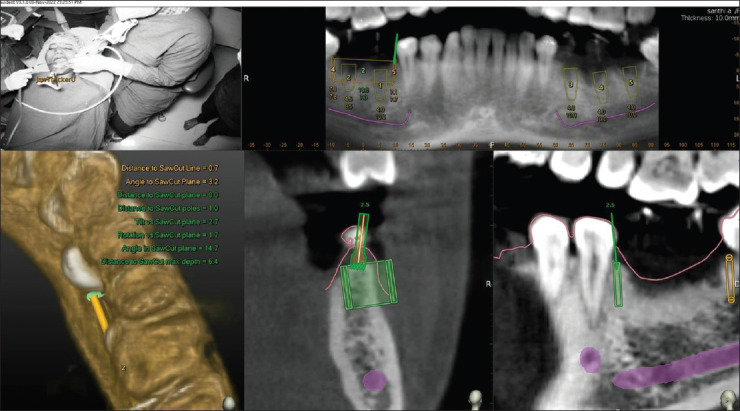

Conventional alveolar ridge splitting (ARS) technique involves a significant risk which may prove problematic. This case report presents the first documented application of dynamic navigation system (DNS)-guided ARS, demonstrating a precise approach to implant placement in a challenging anatomical scenario. A 37-year-old partially edentulous patient presented with missing mandibular posterior teeth. Clinical examination revealed a deficient alveolar ridge. Cone-beam computed tomography evaluation showed a Siebert's Class I resorbed ridge with 2.5 mm width and bone density ranging from 870 to 1040 Hounsfield Units in the #46 and #47 regions. Creating and designing three-dimensional virtual guide slits and implant planning using DNS were done in patient with insufficient bone width in the mandibular molar region. Piezoelectric ARS, osteotomy preparation with implant placement was done. 0.70 and 0.26 mm deviations at #46 and 0.50 and 0.01 mm deviations at #47 were observed at implant entry and implant apex, respectively. The angular deviations were optimal. ARS using real-time navigation appears to be an efficient and promising technique.